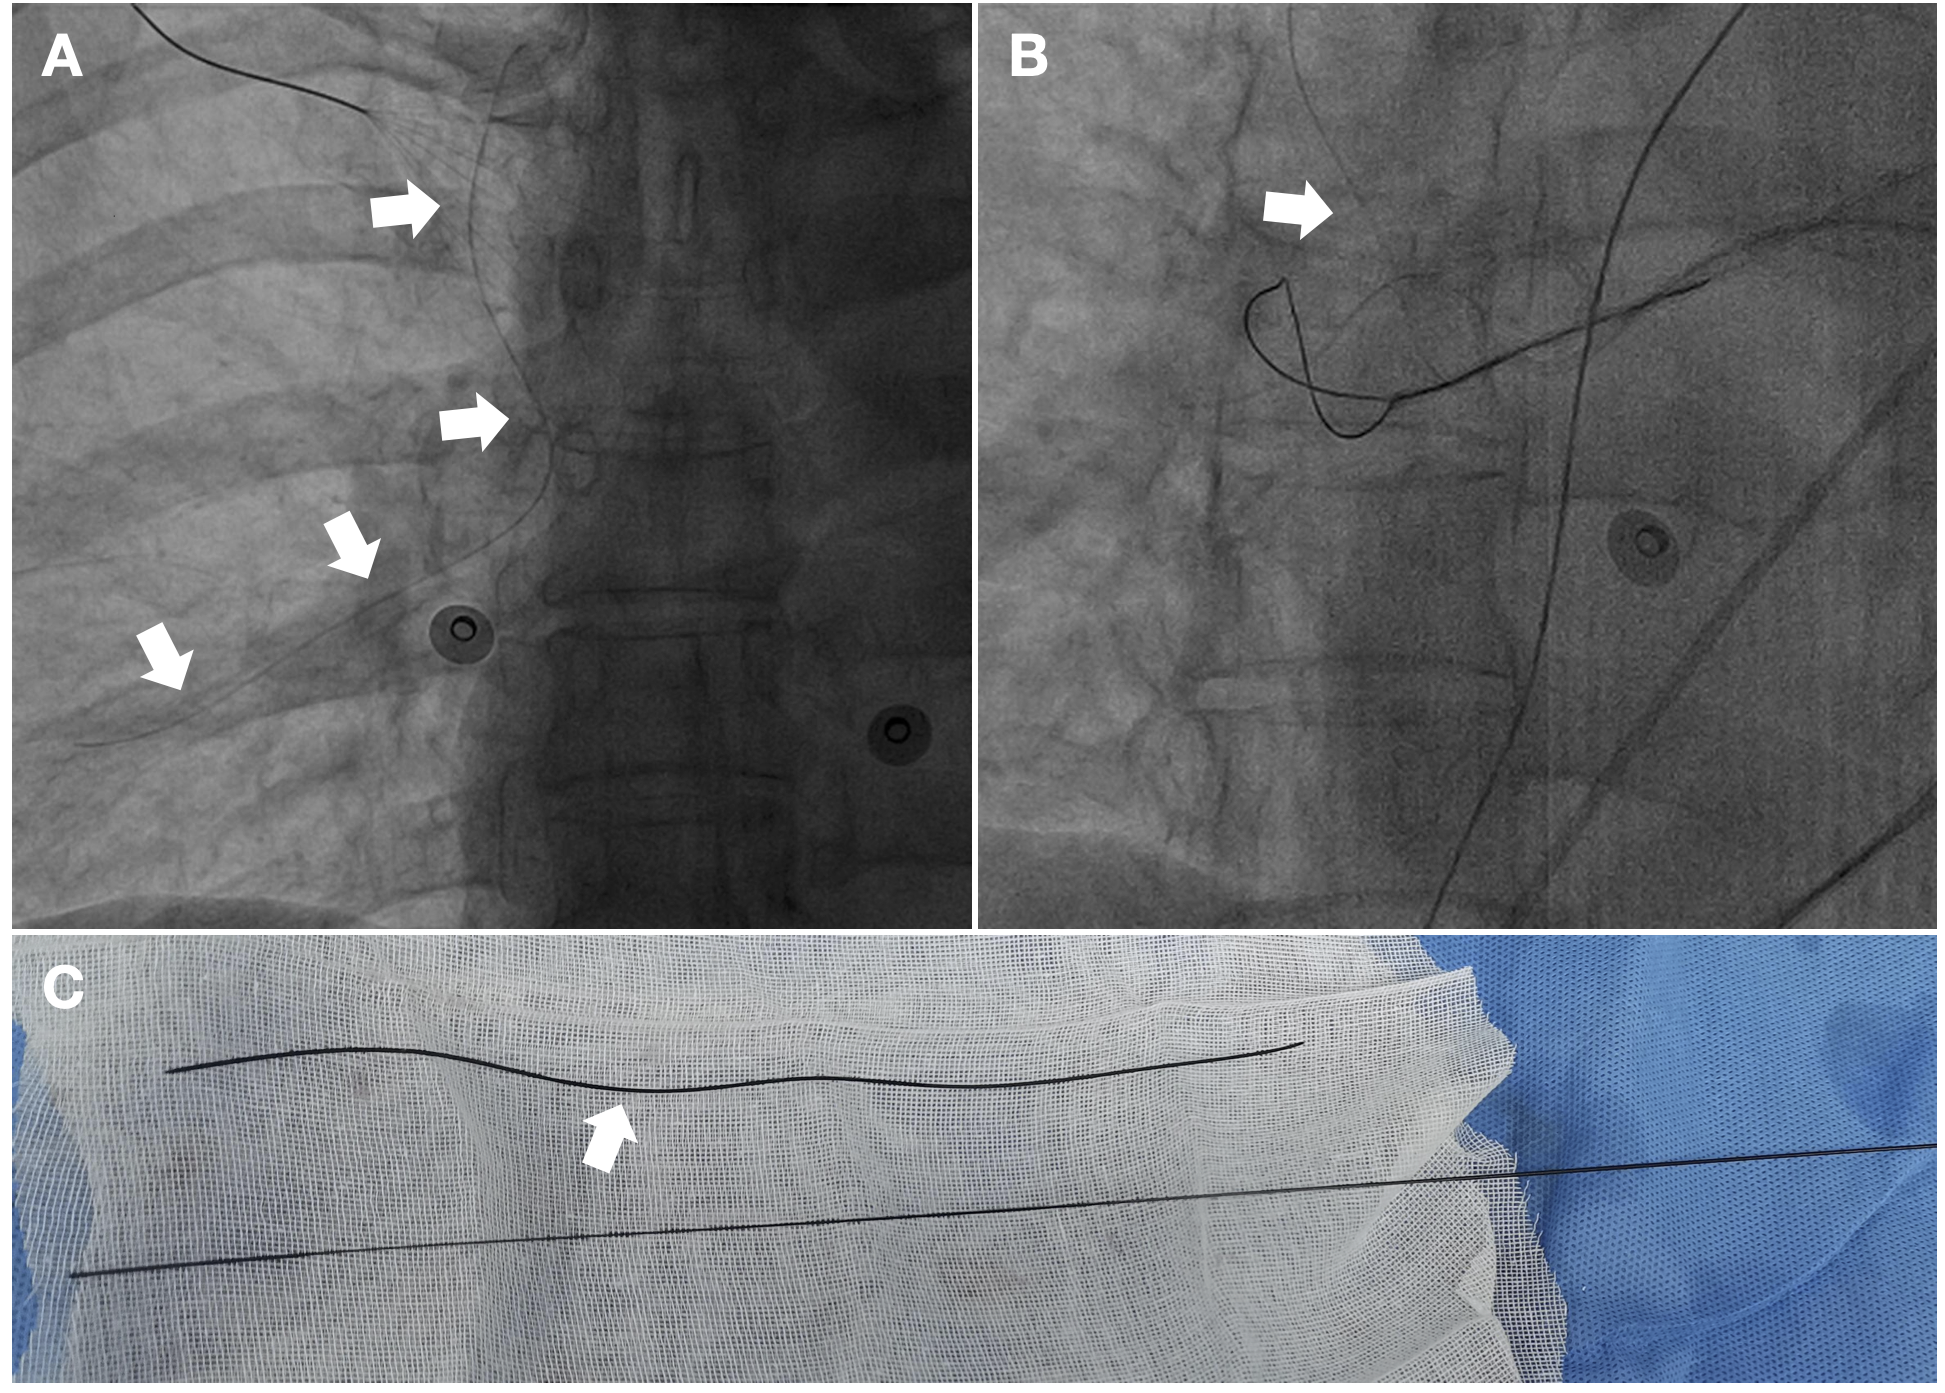

A 62-year-old woman with atrial fibrillation was admitted to Sichuan Provincial People’s Hospital, and radiofrequency ablation therapy was planned. After femoral venous puncture, X-ray fluoroscopy showed a slim-line shaped wire that was floating in the right pulmonary artery (Figure, A; Video 1). To remove the wire, a pigtail catheter was placed in the right pulmonary. Then, the catheter was rotated to pull one part of wire back into the trunk of the right pulmonary. Finally, the wire was successfully captured by a snare (Figure, B; Video 2).

To our surprise, we discovered that this wire was the hydrophilic coating of the puncture guide wire (Figure, C). How has this happened? An inappropriate puncture procedure was considered as the cause of the complication; the interventional physician used a steel puncture needle (ArcRoyal) instead of matched puncture needle (Terumo). When the guide wire was pulled back through the steel needle, the hydrophilic coating may have been stripped (Video 3). In light of this potential complication, physicians should pay close attention when using hydrophilic coating guide wire during vascular puncture.